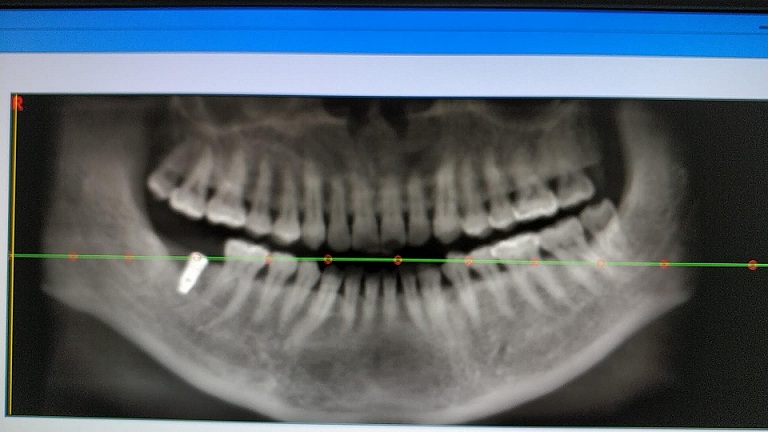

术后全景片

手术历时约20分钟,术中微创操作,患者完全无痛,术后无不良反应,整个诊疗过程舒适、安全、精准。